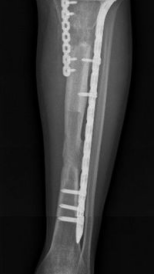

多年来,贵州航天医院各科室紧跟医学前沿,不断强技术、补短板,大力开展新技术、新项目,完成了许多高精尖、高难度、本地区“首例”的技术,填补了医院医疗技术空白,满足了群众日益增长的医疗需求。 贵州航天医院骨科率先在遵义地区开展骨搬移技术,截至目前,已治愈慢性骨髓炎、感染性骨不连、骨缺损、脉管炎、糖尿病足患者200余例,糖尿病足治疗保肢率达到98%。 本期,我们将为大家带来骨科特色技术——骨搬移技术(Ilizarov)。 案例分享 一名59岁的患者,身患糖尿病12年,在来我院3个月前出现了右脚溃烂的症状,来院就诊时,患者的右脚十分红肿,右脚脚趾坏死,伤口处不断流出黑红色脓液,情况十分严重。在接诊到患者时,骨科专家团队高度重视,立刻为患者完善了CT血管造影(CTA)等相关检查,诊断为:2型糖尿病,糖尿病周围血管病变,右糖尿病足。 术 前 考虑到患者情况比较严重,为最大限度保证患者肢体完整,科室专家团队进行了严格的讨论评估,为患者制定了骨搬移技术治疗方案,在征得患者及其家属的同意后,成功通过搬移骨块为患者进行治疗,促进患者病变肢体血管再生。 胫骨横向骨搬移外架固定 清除感染病灶 术后调节外架,通过搬移骨块 促进患肢血管再生 患者在术后三周前来换药,观察到感染得到进一步控制;术后六周复查,患者病变处已愈合,进行CT血管造影(CTA)后可明显观察到足部血管再生。 术后3周 术后6周愈合 CT血管造影见足部血管再生 糖尿病患者全身与局部的问题互为影响,形成恶性循环,糖尿病足溃疡创面迁延不愈,常见干性坏疽、湿性坏疽、趾坏死、深且大的溃疡以及骨髓炎等症状,还可导致脓毒血症,以往为保全生命,患者被迫选择一次或多次截肢。骨搬移技术的发展进步,能在血糖有效控制、局部有效清创下,有效促进患肢微血管再生,改善患肢血供,达到糖尿病足更快治疗康复的目的,并能根据病变情况最大限度的保障患者肢体完整。 什么是骨搬移技术 骨搬移技术是通过使用专用的骨外固定器固定骨段,每天缓慢牵拉,在牵拉搬移过程中,骨段尾部形成新骨及新的软组织,从而修复骨骼缺损及软组织缺损。是治疗大段骨缺损、骨不连、骨感染、肢体畸形的金标准方法,也用于治疗脉管炎、糖尿病足等肢体缺血性疾病。 骨感染缺损 切除感染段 搬移骨段 新骨形成 骨感染根治愈合 骨搬移技术原理 生物组织在持续、稳定、缓慢牵拉下,能刺激细胞分裂、组织再生,骨外固定技术运用该原理,通过持续缓慢调节外固定器形成牵拉张力,促进牵引成骨与相邻组织再生,如神经、血管、肌肉、皮肤等再生,达到治疗大段骨缺损、肢体缺血如糖尿病足等疾病的目的。 骨搬移技术优势 (一)除治疗骨缺损、骨不连外,有更广的适用范围,利用组织再生、血管再生等特性,能大量运用于肢体畸形的矫形、糖尿病足等的治疗。 (二)治疗效果确切,重建肢体外型和功能,极大降低截肢率和残疾率。 (三)明显提高了患者生活质量,极大减轻其家庭及社会负担。 肢体畸形的矫形 慢性骨髓炎 骨段切除 术后1年 濒临截肢的脉管炎术后6周 难愈创面术后3周 贵州航天医院骨科 专家团队 赵学平 骨科主任 主任医师 临床擅长:从事骨科临床工作30余年,对骨科常见疾病的诊治具有丰富的临床经验。 世界中医药联合会脊柱康复专业委员会常务理事,中华中医药学会整脊分会常务委员,中国中西医结合学会骨伤科分会肢体矫形功能重建与康复专家委员会常务委员,中国研究性医院学会骨科创新与转换专业委员会关节外科学组保髋工作委员会常委,中国康复技术转化及发展促进会骨外科与康复技术转化专业委员会常务委员,泛珠三角区域运动医学联盟(PPRD-SMA)理事会常务理事,中国研究型医院学会运动医学专业委员会委员,贵州省中医药学会整脊分会副主任委员,贵州省中西医结合学会银质针专业委员会副主任委员,贵州省康复医学会骨与关节专业委员会常务委员,贵州省人民医院骨科专科联盟常务理事,贵州省康复医学会骨内科专业委员会常务委员,中华医学会贵州省骨科学会委员,贵州省康复医学会脊柱脊髓专业委员会常务委员,贵州省运动医学分会委员,贵州省康复医学会骨与软组织肿瘤专业委员会委员,遵义市医学会创伤分会副主任委员,贵州省康复医学会骨内科专业委员会遵义地区分会常务委员,遵义市医疗事故鉴定、伤残鉴定、工伤鉴定、司法鉴定专家。 长期从事骨科临床研究及教学工作,在国家级、省部级杂志发表论文20余篇,SCI论文2篇,参与主编骨科专著2部,主持省部级科研项目2项,参与指导省部级、市级科研项目6项。 陈明勇 骨科副主任 副主任医师 临床擅长:从事创伤骨科工作约20年,对骨缺损、骨不连、骨肿瘤、肢体畸形等的肢体矫形重建及功能重建,慢性化脓性骨髓炎的根治治疗、糖尿病足的保肢治疗、快速康复理念(ERAS)下的老年骨折的诊治,四肢复杂骨折的诊治,四肢骨折等微创手术治疗具有丰富的临床经验。 2004年毕业于遵义医学院临床专业,曾在中国人民解放军总医院、广西医科大学第一附属医院、上海第六人民医院骨科进修。中国中西医结合学会骨伤科专业委员会横向骨搬移治疗糖尿病足及微血管网再生学组首届委员,遵义市医学会创伤分会常务委员。 瞿 辉 骨科 副主任医师 临床擅长:对骨科的常见病、关节外科、脊柱外科及运动医学疾病的诊治具有丰富的临床经验,熟练掌握骨科手术操作技术。 毕业于遵义医学院临床医学系,2005年前往广州中山大学第一附院骨显微医学部进修学习,2011年前往成都华西医院进修学习,并多次在省内外学习骨科相关知识,是中华医学会骨科分会会员。 赵兴东 骨科 主任医师 临床擅长:擅长骨科的常见病及各种创伤、四肢骨折创伤修复、骨感染、手足疾病的诊治和手足体表畸形的矫形整复,熟练掌握骨科四肢骨病及创伤的手术操作技术,尤其在四肢关节复杂性损伤、手足外伤、组织缺损创面、难治创面的皮瓣修复方面及平足、高弓足矫形方面及四肢慢性疼痛诊治、康复方面具有丰富的临床经验。 硕士研究生,毕业于遵义医学院临床外科系,2015年前往山东省立医院手足外科进修学习;遵义市医学分会创伤分会第一、二届委员,遵义市手外科医学会第二委届员会常务委员;在省级及省级以上期刊发表文章9篇,参编著作2部,参与主持并完成市级课题1项,参与市级课题2项、省级课题1项。 张俊凯 骨科 副主任医师 临床擅长:从事骨科临床工作28年,对创伤骨折、骨感染、骨缺损、骨不连等外科诊治,四肢骨折的微创手术治疗,四肢复杂骨折(如关节内粉碎性骨折、多发骨折等)的损伤控制及手术治疗等具有丰富的临床经验。 1995年毕业于遵义医学院临床专业,2009年前往复旦大学附属医院骨科进修1年。 卢懿明 骨科 副主任医师 临床擅长:从事骨科工作18年,对创伤骨折、四肢骨折的微创手术治疗、四肢复杂骨折(如关节内粉碎性骨折、多发骨折等)的损伤控制及手术治疗,尤其是髋部骨折的PFNA等微创技术,踝关节骨折、膝关节周围骨折的Mipo微创技术等具有丰富的临床经验,开展了4项新技术,发明6项新型专利技术。 2005年毕业于遵义医学院临床专业,2017年,前往南方医科大学第三附属医院骨科进修半年,回院后运用Mipo技术对骨干骨折及干骺端骨折的治疗技术,同时积极开展骨盆骨折、髋臼骨折腹直肌外侧切口的应用;发表了多篇专业论文,经常参与省内外学术交流会授课,获得医院荣誉称号多个。 邬夏荣 骨科 副主任医师 临床擅长:从事骨科工作16年,对四肢复杂骨折、骨肿瘤的诊治,尤其是足踝创伤、慢性踝关节损伤、平足症等诊疗具有丰富的临床经验。 2006年毕业于遵义医科大学临床医学专业,曾在陆军军医大学西南医院进修学习,发表多篇骨科学术论文。 余德怀 骨科 副主任医师 临床擅长:从事骨科工作10余年,对运动医学、骨关节、脊柱外科常见病、多发病的诊治具有丰富的临床经验。 硕士研究生,2011年毕业于遵义医学院临床医学专业,曾前往遵义医科大学附属医院运动医学专业进修学习;是贵州省医学会运动医学分会青年委员,西部关节镜联盟委员;发表多篇骨科学术论文。 冯 乾 骨科 副主任医师 临床擅长:从事骨科工作近20年,熟练掌握骨科多发病及常见病的诊治,尤其对脊柱退变性疾病的诊断及治疗具有丰富的临床经验,主要研究脊柱微创相关治疗方式,能熟练开展椎间孔镜及VBE。 曾前往北京大学第三医院进修学习疼痛及椎间孔镜、首都医科大学友谊医院专业进修脊柱内镜;是贵州省康复医学会第三届脊柱脊髓专业委员会委员;发明专利3项、发表脊柱外科专业论文多篇。 张艳金 骨科 副主任医师 临床擅长:从事骨外科工作16年,对复合伤、多发伤的救治、四肢骨干骨折、关节周围骨折、骨肿瘤、骨髓炎等诊治具有丰富的临床经验。 中共党员,硕士研究生,2006年本科毕业于山西医科大学第二临床医学院,2011年研究生毕业于北京军区总医院;在“老年COPD患者合并髋部骨折的诊治”国际合作课题组研究两年,在老年髋部骨折的诊治方面具有丰富的经验,并发表论文6篇;承担遵义市级课题1项;承担遵义医科大学的临床教学工作,获得遵义医科大学优秀带教老师荣誉。编撰有《骨科疾病诊疗精粹》一书,开展2项新技术,编撰地方规范《务川自治县创伤骨科常见疾病诊疗规范》一书。 赵小锋 骨科 副主任医师 临床擅长:从事骨科临床工作11年,对骨科常见病、多发病诊疗有较为丰富的临床经验,擅长脊柱相关疾病诊断及治疗,尤其是颈、腰、腿疼痛疾病诊断及治疗,擅长胸腰椎骨折微创经皮穿刺内固定术、经皮穿刺椎体成形术、经皮穿刺脊柱内镜下腰椎间盘摘除术、单纯开创腰椎间盘摘除术、腰椎滑脱复位椎间植骨椎融合内固定术、腰椎管狭窄减压融合内固定术及人工髋、膝关节置换术等。 2012年毕业于遵义医学院外科学专业硕士研究生,2019年参加“遵义市115医学人才精英计划”于上海交通大学第一附属医院培训学习,2023年于北京大学第三人民医院脊柱外科进修学习,曾获得遵义市优秀医师荣誉称号。 遵义市手外科第一届委员,遵义市医学会创伤分会第一届委员,遵义市医学会创伤分会第二届委员,贵州省康复医学会第三届脊柱脊髓专业会委员,遵义市医学会烧伤与整形外科学分会委员,发表论文5篇,其中国家级核心期刊1篇,SCI论文1篇,主持市级课题1项并结题,参与市级课题2项。 贵州航天医院骨科简介 基本情况 贵州航天医院(原3417医院)骨科组建于1968年,前身是以创伤和断肢(断指)再植闻名于世的上海市第六人民医院骨科,中国断肢(断指)再植的奠基者、中科院院士陈仲伟等著名专家、学者多次莅临科室指导医疗、教,是贵州省最早拥有专业骨科技术科室之一,在70年代开展了贵州省首例断肢(断指)再植手术。组建50余年来,诊治患者已逾百万,挽救了无数的伤病员,成为了保障遵义地区人民群众健康的重要支撑。 经过几代人的不懈努力,今天的骨科,已由创伤骨科发展至骨病、骨肿瘤、骨结核等领域,现有脊柱外科、关节外科、四肢创伤、手足外科四个亚专科,成为了集医疗、教学、科研于一体的综合学科,是贵州省临床重点专科、遵义市临床重点专科、遵义市骨科临床医学中心、遵义市基层骨科专科联盟理事长单位。 科室目前开放床位110张,共有医护人员50余人,副高级以上专家18人,硕士研究生15人。拥有一流骨科医疗设备多台,每年不定期选派优秀技术骨干到全国各大知名医学院校进修、学习、参观、交流,并邀请国内、国外知名专家教授来院进行交流、指导,通过不断引进国内外先进的诊疗技术,科室医疗技术水平稳步提升,为广大人民群众提供了优质的医疗服务。 专科特色 骨一科 (一)骨缺损、骨不连的肢体与功能重建 胫骨横向骨搬移技术治疗糖尿病足: (二)慢性骨髓炎的根治治疗 (三)肢体缺血性疾病如糖尿病足、脉管炎的保肢治疗 (四)皮瓣修复 (五)复杂创伤的治疗 (六)老年髋部骨折及小儿骨折快速手术 老年髋部骨折: 骨二科 (一)胸腰椎骨折微创经皮椎弓根螺钉固定术 (二)老年性骨质疏松性患者腰椎滑脱脊柱内固定术(骨水泥螺钉) (三)V形双通道脊柱内镜技术(VBE)腰椎融合术治疗腰椎退行性疾病 (四)老年性骨质疏松性骨折(PVP/PKP)术 (五)人工髋关节置换术 (六)双侧股骨头坏死人工全髋关节置换 (七)右侧全髋置换术后假体周围骨折翻修 (八)人工膝关节置换术 (九)人工膝关节假体松动翻修 (十)关节镜技术 传统手术切口 关节镜技术切口 诊疗范围 骨一科 1.四肢创伤、矫形。 2.手、足踝外科。 骨二科